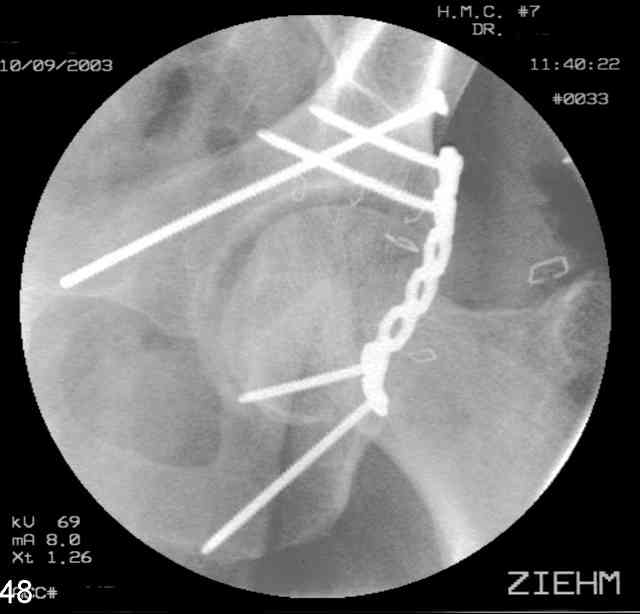

Understand that this is no simple fracture but in the same breath is very common and can be very routinely-simplistically treated without a variety of complicated and variable scenarios...keep it simple...turn him prone, clean him up, do a nice exposure, protect the nerve, remove the debris, save it and sort it out if you can, clean the fracture lines, manipulate and clamp the transverse, hold it how you choose (I'd recommend a percutaneously inserted 3.5mm antegrade medullary lag screw), remove the clamp, reduce the

small or impacted fragments to the head, reduce the wall, and support the wall and transverse with a balanced 3.5mm contoured reconstruction plate.

I'll include a few images of a similar injury in a similarly large male patient. This patient "showed up" in our ER c/o hip pain 2 months after being treated in the lateral position, without a quality reduction, without an anterior column transverse supporting implant, with an unbalanced plate applied too medially, with insufficient caudal segment fixation...it took over 8 hours and a 3+ l blood loss to debride the callus from front then

back, excise the HO, release his sciatic nerve, reduce the head-transverse-wall, and fix it...and now it's a staging procedure.

The 2nd example is of a motorcyclist with a transverse fracture-dislocation...he had a closed attempted reduction and placed in traction but the manipulative reduction was not concentric (not unusual for this injury pattern)...so the traction was adjusted to be just enough to disengage the head from the fracture (12#) until he could be cleared for surgery one day after injury...he was treated "urgently" then with a prone KL, clean the fracture, reduce and clamp it, screw it, support with a balanced plate, close, and enjoy...2-3hours, 400cc EBL, blah, blah, blah..